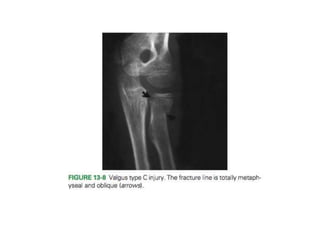

3. Type C—Fractures involving only the proximal radial

metaphysis